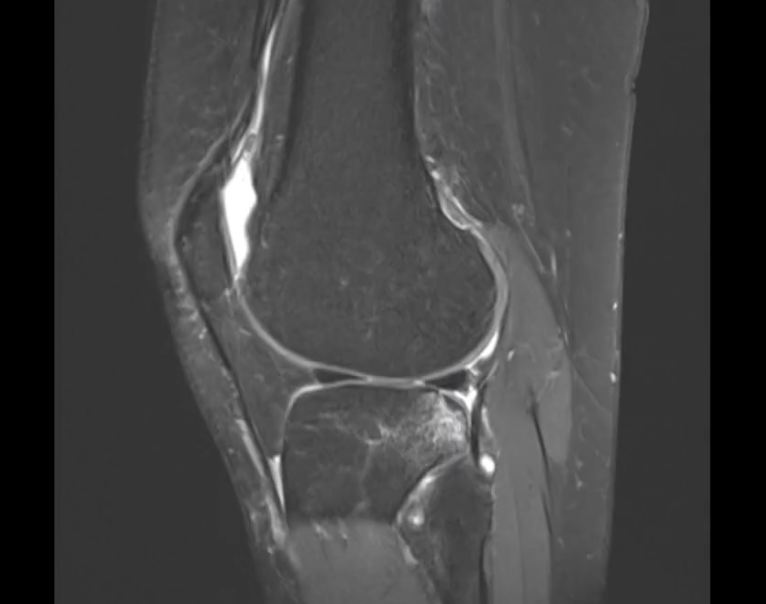

Discuţie caz nr 97: Examinarea efectuată posttraumatic – accident la ski: se evidențiază creștere de volum a LIA ce prezintă hipersemnal difuz și întreruperea completă a continuității fibrilelor în jumătatea proximală. La nivelul cornului posterior al meniscului intern se evidențiază o bandă în hipersemnal în plan oblic sagital ce interceptează suprafețele articulare superioară și inferioară. La nivelul jumătății lateral a platoului tibial predominent posterior, dar și cu arie de proiecție mai mică la nivelul condilului femural extern, se evidențiază plaje de edem osos cu traiecte de microfractura în interior.